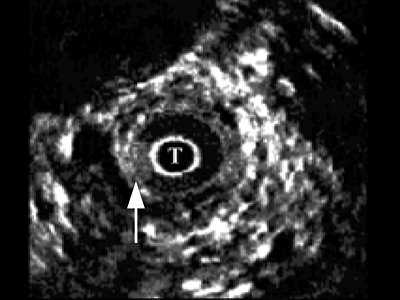

В мембранозном отделе (рис. 3) спонгиозная ткань не определяется, визуализируются повышенной эхогенности пластинка тазовой фасции, далее мочеполовая диафрагма с проходящими сосудами. При проведении датчика в область простатического отдела хорошо определяется предстательная железа, ее транзиторная, центральная, частично периферическая зоны, капсула.

Рис. 3. Эхограмма нормального мембранозного отдела мочеиспускательного канала.